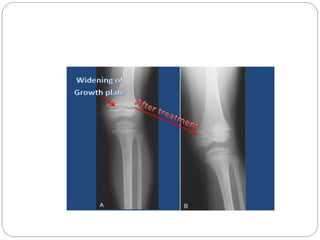

 Failure of the physeal cartilage to calcify and

undergo normal endochondral ossification leads

to an increased thickness of the physis and a

hazy appearance of the provisional zone of

calcification .

 The widened growth plate is particularly suspect

for rickets, which differentiatesthis rare condition

from the more common physiologic angular

deformities of the lower extremities .

 The metaphysis abutting the physis is brushlike in

appearance,with islands or columns of cartilage

persisting wellinto the metaphysis .

 The metaphysis also appears cupped or flared.

The bones have an osteopenic appearance

overall, with thinning of the cortices.

 Treatment

 Rickets is treated by the administration of vitamin

D under the supervision of a pediatric specialist in

metabolic bone disease.

 The usual course of treatment is 6 to 10 weeks.

 After 2 to 4 weeks, radiographs show

improvement in mineralization.